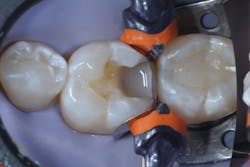

Caries lesions were removed and air abrasion was employed to remove impurities on the unprepared tooth surfaces and create increased surface area for bonding. Preparation of the class II carious lesions revealed demineralization on the adjacent tooth structure (figure 3). When lesions such as these are discovered, dentists are often at a crossroads whether to intervene or monitor the area for progression. It is my experience that these early caries lesions can be predictably arrested with resin infiltration (figure 4), and that no intervention usually results in the progression of caries.

In this case, lateral access was achieved by the preparation of the adjacent teeth as part of the proposed treatment plan. Early caries lesions that are noted on radiographs that are not accessible in cases such as this one can be accessed by placing an orthodontic spacer. This patient was restored with direct composite bonding (figure 5) and these restorations have proven to have a favorable long-term outcome (figure 6).